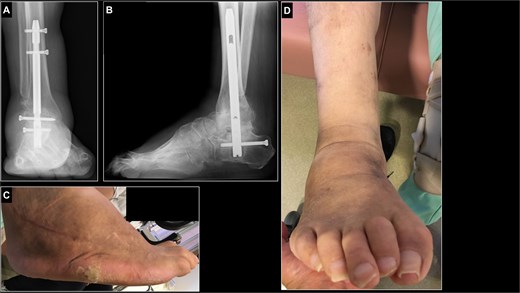

Postoperatively, the ankle was immobilized with a cast and non–weight bearing was maintained for 5 weeks. After removal of the cast and Kirschner wires, partial weight bearing with an ankle orthosis and gait training were initiated. Full weight bearing was permitted 8 weeks after surgery. Three months postoperatively, the patient achieved stable walking with a walker and was discharged. At 1 year postoperatively, radiographs confirmed union at the osteotomy site and maintained correction of the varus deformity (Fig. 5A and B). The painful callosities had resolved (Fig. 5C and D). Functionally, the patient was able to walk without pain using a walker for outdoor ambulation. At 3 years postoperatively, the patient has remained free from recurrence of the deformity, and the clinical scores have improved markedly (Table 1). The JSSF ankle/hindfoot score improved from 4.0 to 66.0, the JSSF midfoot score from 0.0 to 73.0, and the self-administered foot evaluation questionnaire (SAFE-Q) total score from 89.2 to 366.0 [12, 13].

Postoperative radiographs and photographs of the right foot 1 year after surgery. (A, B) radiograph of right ankle in a weight-bearing position showed the fusion of osteotomy site and sustained plantigrade alignment. (C, D) The callosities of lateral aspect of foot had almost come off.